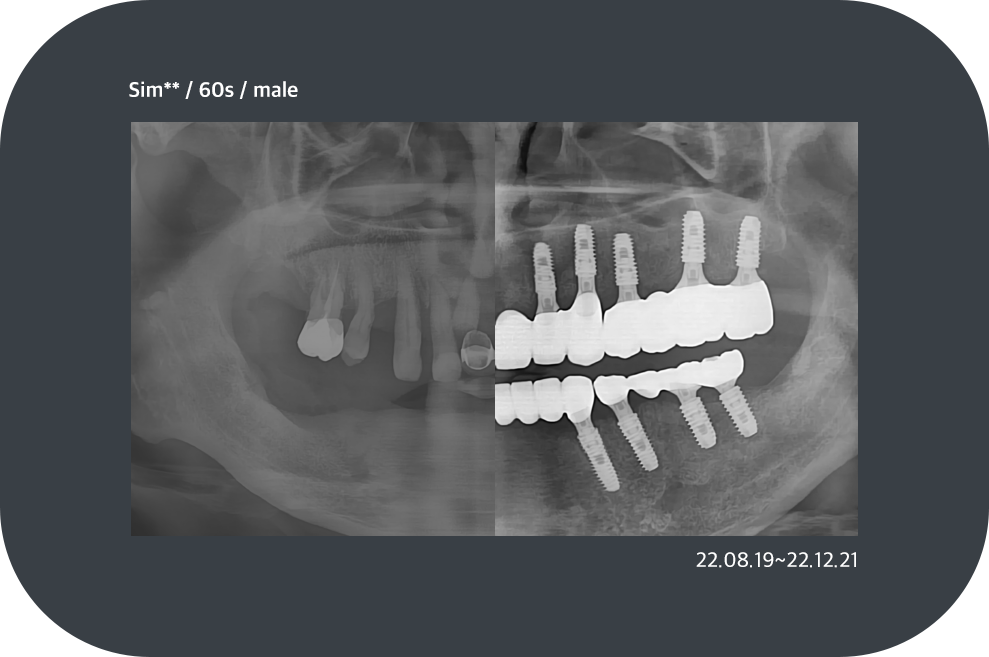

치료사례

임플란트 치료사례

implant_case01

implant_case02

implant_case03

implant_case04

*모든 증례 사진은 의료법 제23조, 제56조에 의거하여, 당사자의 동의하에 게시하였습니다.

*치료 사진은 모두 본원에서 치료한 환자분의 사진입니다.

*치료 사진은 모두 동일인의 사진이며, 동일조건에서 촬영하였습니다.

*개인의 차이에 따라 시술 및 수술 후 부작용이 발생할 수 있으며, 의료진과 충분한 상담을 받으시기 바랍니다.